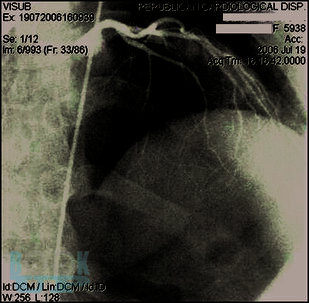

В пособии представлены особенности клиники и диагностики врождённой коронарной патологии – мышечного мостика, наличие которого при определённых условиях может стать причиной острого коронарного синдрома и внезапной сердечной смерти (на втором месте после гипертрофической кардиомиопатии) у молодых людей без факторов риска ишемической болезни сердца. Последовательно изложены возможности повышения информативности функциональной пробы с физической нагрузкой и стресс-эхокардиографии в выявлении ишемии миокарда, вызываемой коронарной аномалией. Далее показана эффективность медикаментозных средств, чрескожного вмешательства, хирургической коррекции у больных с мышечными мостиками.